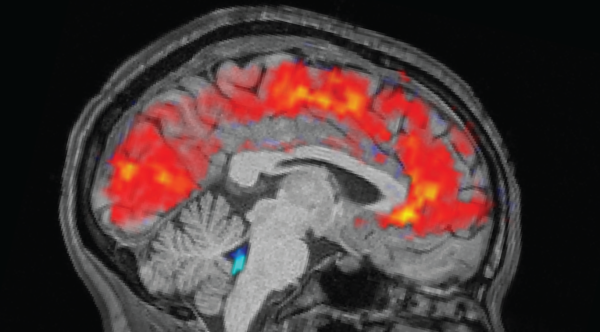

Investigators can now determine the rate at which your entire body is aging using simply a glimpse of your brain, claim researchers in a fresh study.

The scientists, who revealed their conclusions on July 1 in the journal Nature Aging, have shaped a yardstick of physical aging relying on brain MRIs. The group suggests the instrument may anticipate a person’s future chance of cognitive decline and dementia, ongoing conditions like cardiac disease, bodily vulnerability and untimely demise.

They measured the processed brain information against other details amassed from the participants concurrently, such as tests regarding physical and mental deterioration, subjective health conditions, together with indicators of facial aging, such as lines. They declared that increased losses in those areas were linked to an accelerated rate of aging, in general, and therefore tied facets of the brain details to those estimations. They labeled their resulting formulation “Dunedin Pace of Aging Calculated from Neuroimaging,” or DunedinPACNI.

“[DunedinPACE] has seen broad acceptance by trials possessing available epigenetic data,” Hariri voiced. “DunedinPACNI now grants trials void of epigenetic data but containing brain MRI the capacity to gauge accelerated aging.” The researchers juxtaposed DunedinPACNI to DunedinPACE head-on, discovering that they produced comparable results.